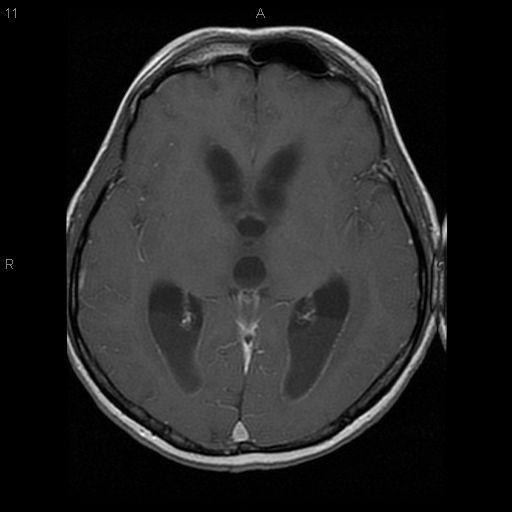

We report a fatal case of meningitis, caused by Fusobacterium necrophorum, secondary to otitis media in an alcoholic male. Diagnosis was delayed due to the typical slow growth of the organism. The clinical course was complicated by encephalitis and by hydrocephalus. The patient failed to respond to metronidazole and penicillin. The patient died on day 12 from increased intracranial pressure and brain stem infarction.

我们报告一例由坏死梭杆菌引起的致命性脑膜炎病例,该病例继发于一名酗酒男性的中耳炎。由于该病菌典型的缓慢生长特性,诊断被延误。临床过程因脑炎和脑积水而复杂化。患者对甲硝唑和青霉素治疗无反应。患者于第12天因颅内压升高和脑干梗死死亡。